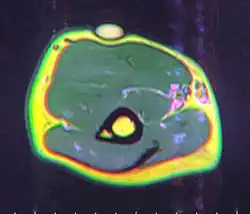

A physical exam is typically the easiest way to diagnose it. Rarely, a tissue biopsy or imaging may be required. The imaging modality of choice is magnetic resonance imaging (MRI) because it has superior sensitivity of distinguishing it from liposarcoma as well as mapping the surrounding anatomy.[22]

-

X-ray of a lipoma -

MRI showing lipoma of the arm -